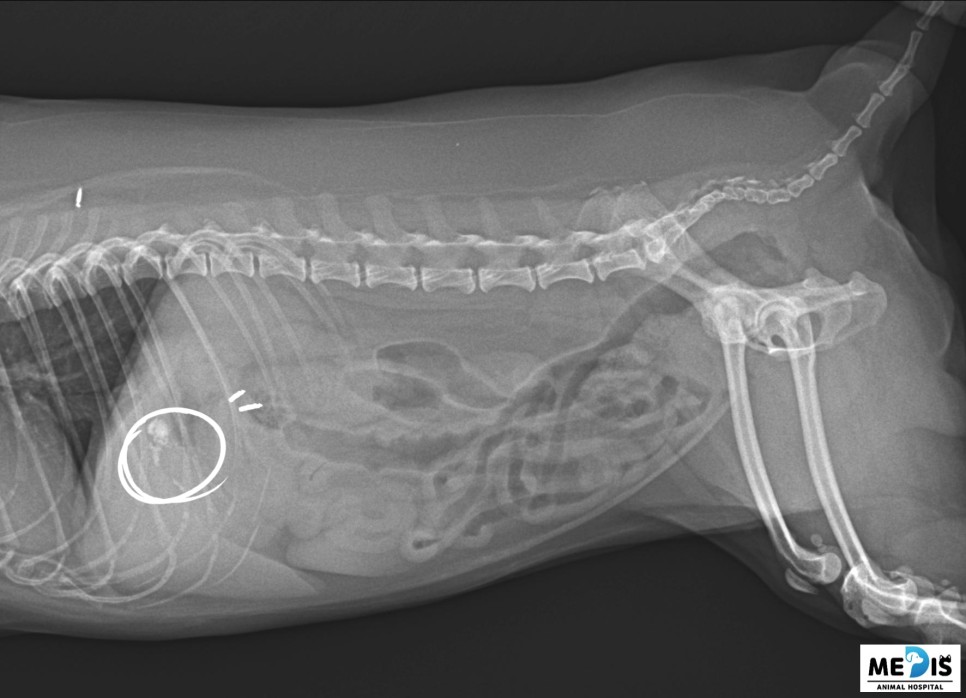

복부 방사선을 촬영했을 때 담낭으로 의심되는 위치에 결석 음영이 관찰되었습니다.